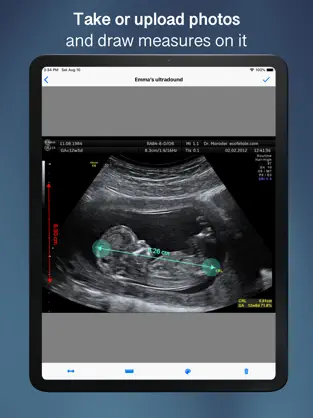

Image Ruler - Measures

Características de Image Ruler - Measures

Screenshots de Image Ruler - Measures